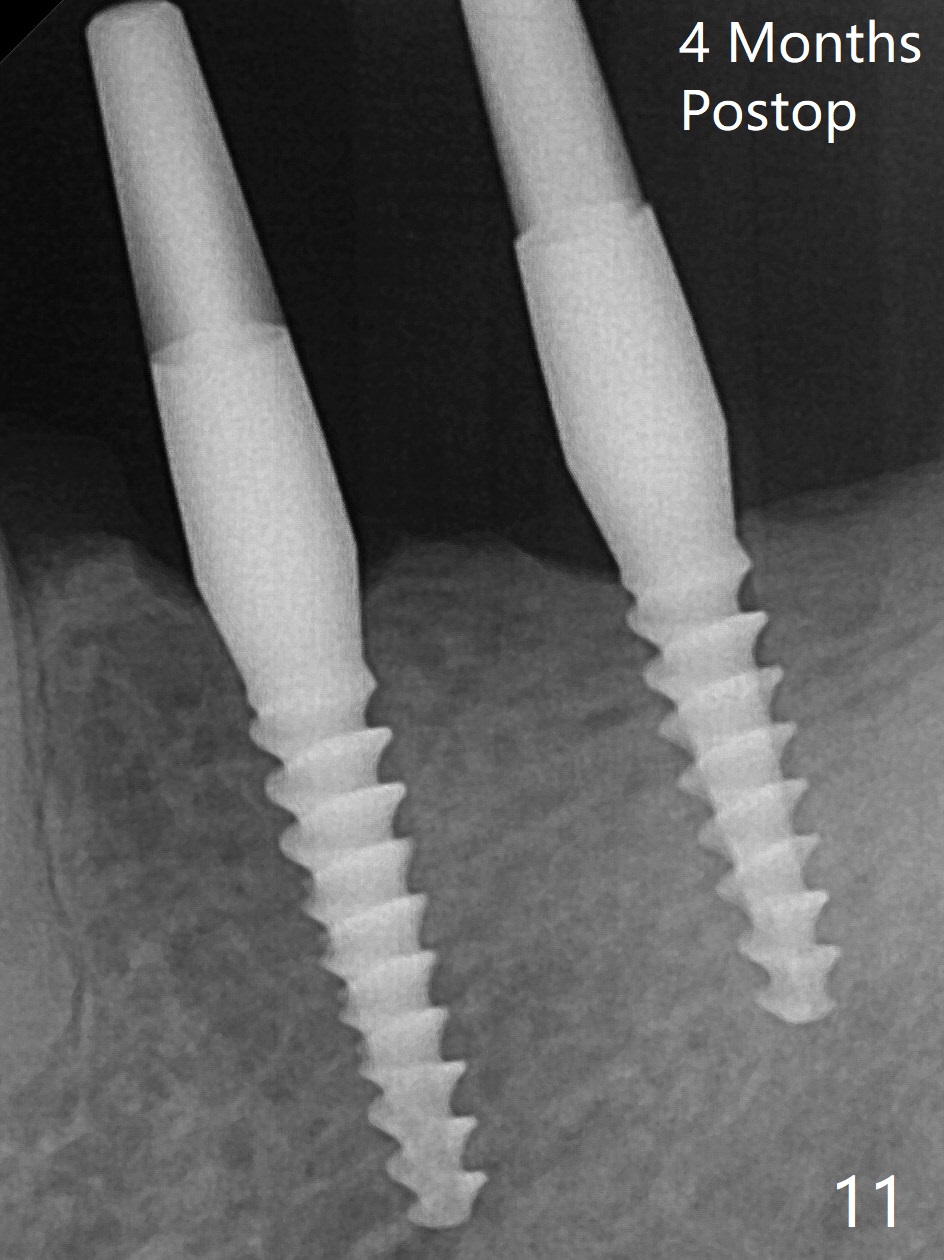

左下第一磨牙(#19)牙槽嵴狭窄,2.2毫米钻头完成导板钻洞后,舌侧骨板开始破裂(图一:<),打消牙槽嵴劈开术念头,放置2.5x8.5毫米一段式植体(图二(8.5毫米是最短植体)),好像离下齿槽神经管还有一定距离,适当植入深些(图四:箭头,15Ncm)。右下中切牙缺牙区牙槽嵴也十分狭窄(图四),最后不得不徒手植入2x8.5毫米植体(图五,六,25Ncm)。如果按设计植入2x12毫米植体,颊侧,或者舌侧骨板更容易穿孔。术后3.5月牙槽嵴下降(图七:箭头),可能术中那里压力太大,今后牙槽嵴钻洞要大。24号牙根尖阴影(图七),完成根管治疗(图八)。19牙位牙槽嵴吸收也严重(图九)。其实术后4个月19牙位牙槽嵴吸收并不严重(图十一)。